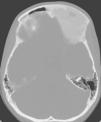

El estudio de resonancia magnética (RM) cerebral evidencia una lesión endomedular, frontoetmoidal izquierda, insuflante, hipointensa, que produce discreto efecto de masa sobre los surcos corticales frontobasales izquierdos (figs. 1 y 2). Para mejor visualización de partes óseas se realiza tomografía computarizada de cráneo y órbitas que muestra como la afectación ósea frontoetmoidal izquierda alcanza el techo de la órbita. La lesión es expansiva, mixta, esclerótica-lítica, y con una atenuación característica en «vidrio deslustrado o cristal esmerilado» (fig. 3). La imagen radiológica sugiere una displasia fibrosa craneofacial. El estudio oftalmológico mostró una agudeza visual y campimetría normales. La serie ósea descartó afectación a otros niveles. Se han realizado controles de RM sin encontrarse progresión tras dos años de seguimiento.